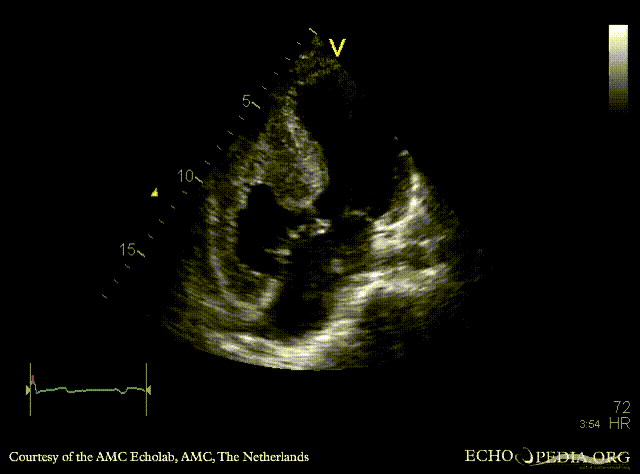

| A4CH: large AVSD

A4CH: Color Doppler signal of AVSD